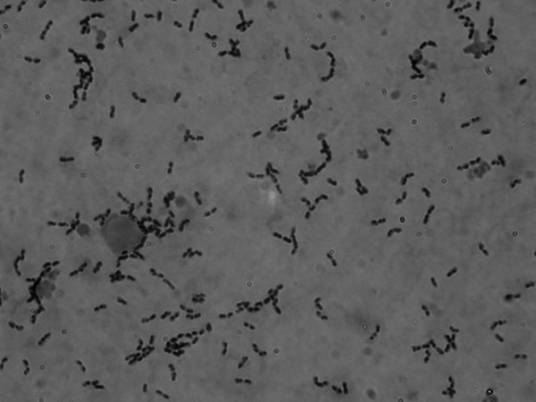

猪链球菌是具有荚膜的一种革兰氏阳性球菌。可根据其细胞壁抗原成分将其大致归类为兰氏分群(Lancefieldgroup D)D群链球菌。根据其荚膜抗原(CPS)的不同,猪链球菌被分为35(1~34型,1/2型)种血清型,其中1,2,7,9型是猪的致病菌。猪链球菌的定植部位为猪的上呼吸道,尤其是扁桃体和鼻腔。部分血清型的猪链球菌具有致病性,主要通过伤口感染。可引起猪的急性败血症(septicemia with sudden death)、脑膜炎(meningitis)、关节炎(arthritis)、心内膜炎(endocarditis)、肺炎(pneumonia)等疾病。部分菌株可引起人类感染,造成细菌性脑炎(bacterial meningitis)或引起中毒样休克综合征(toxic shock-like syndrome)。